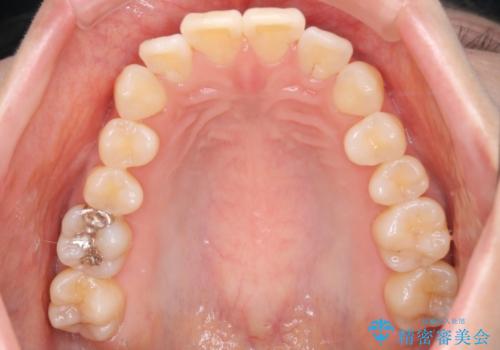

- インビザラインで非抜歯治療を行いました。IPRと拡大をし、叢生、咬合をきれいにしました。

主訴であったかみ合わせを正しい位置に動かし、バランスよくかめるようになりました。矯正治療終了後にメタルインレーをセラミックインレーに替えました。